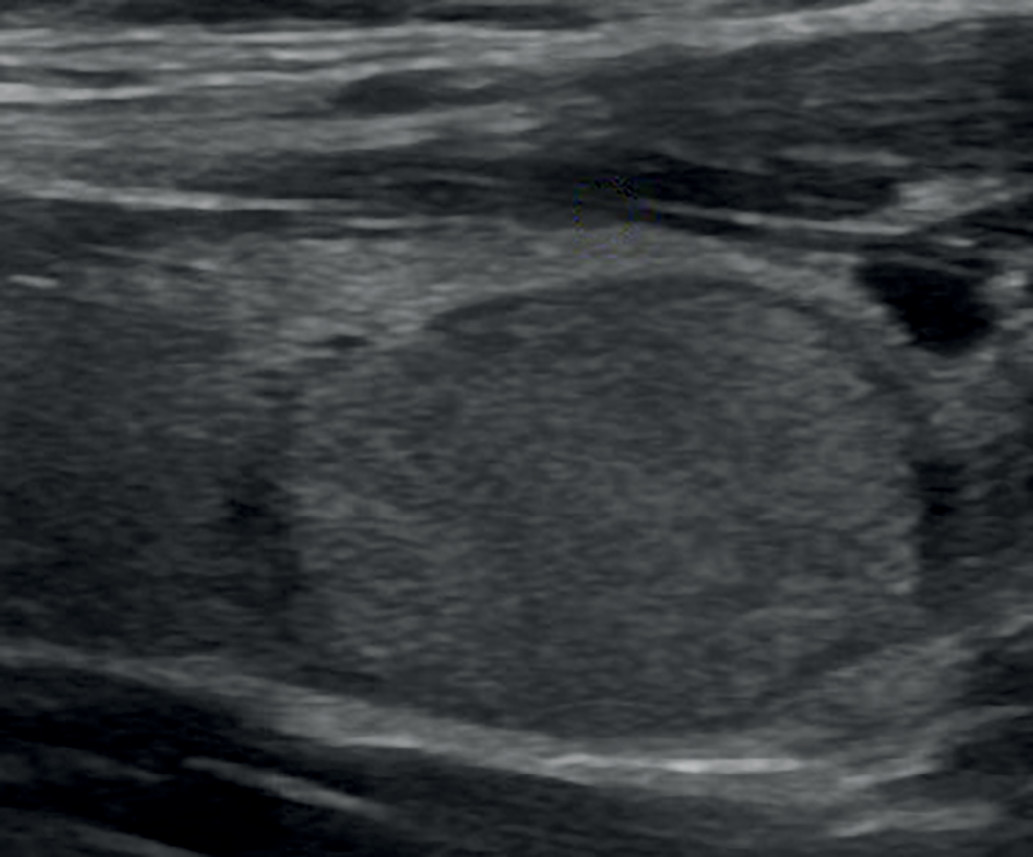

3. Рис. 3. Образование ЩЖ пониженной эхогенности с ровными контурами (EU-TIRADS 4). | |